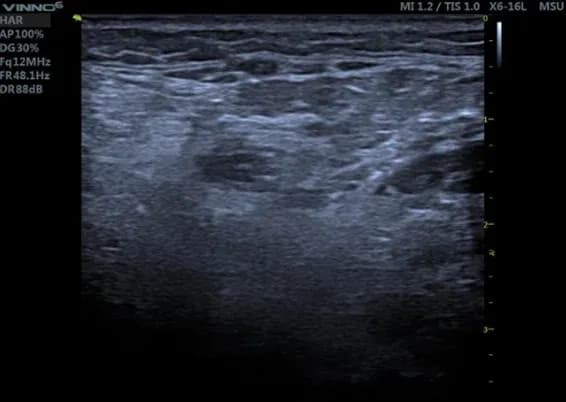

Pathologie am Muskel

Dieses Ultraschallbild zeigt einen durch Polyneuropathie geschädigten Wadenmuskel.